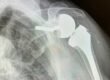

Spalla: quando si deve operare. Spesso sentiamo dire “Mi sono rotto un tendine della spalla” ma quand’è che veramente bisogna intervenire chirurgicamente?

Ci sono due tipi di strutture nella spalla che vanno salvaguardati: i tendini e i legamenti.

Per tendini si intende un gruppo di tendini che formano la famosa cuffia dei rotatori costituita da 4 tendini che ci permettono di muovere la spalla nello spazio.